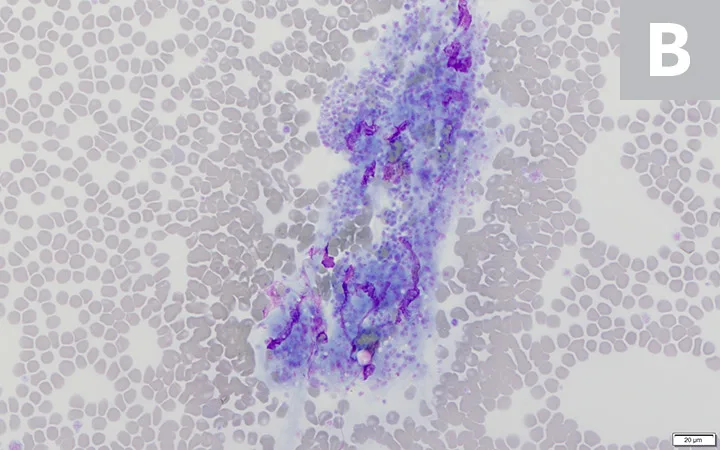

FIGURE 2

Platelet clumps (A; circled) identified at the feathered edge on a blood film from a dog (200× magnification). Higher magnification (B; 600×) of the large platelet clump shown in A. Modified Wright’s stain

Platelet clumps usually indicate the platelets were activated during collection; this is a common finding in all species, especially cats.4,5 However, slow phlebotomy or inappropriate mixing of the EDTA tube can also result in platelet clumps.